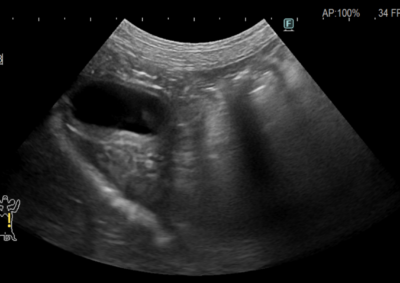

救急・集中治療 注意 ボタンをクリックした先に、治療中および手術中の画像が説明で使用されている場合がございます。 そのような画像に弱い方は閲覧なさらないようお願いいたします。 救急・集中治療 犬の急性膵炎 救急・集中治療 糖尿病合併症(HHS) 救急・集中治療 熱中症 救急・集中治療 糖尿病性ケトアシドーシス 救急・集中治療内視鏡科 食道内異物(ジャーキー) 救急・集中治療 心原性肺水腫 軟部組織外科救急・集中治療 腸閉塞・腸切開 軟部組織外科救急・集中治療 胆嚢粘液嚢腫破裂 救急・集中治療 アナフィラキシーに伴う腹腔内出血 救急・集中治療脳神経科 脊髄梗塞 救急・集中治療内視鏡科 消化管内異物・内視鏡摘出 腫瘍外科救急・集中治療 脾臓腫瘤破裂による腹腔内出血 <1234567> 症例カテゴリー 放射線治療整形外科軟部組織外科脳神経外科内科腫瘍外科救急・集中治療リハビリテーション科腫瘍内科内視鏡科脳神経科呼吸器外科中医・漢方猫の腎移植循環器科